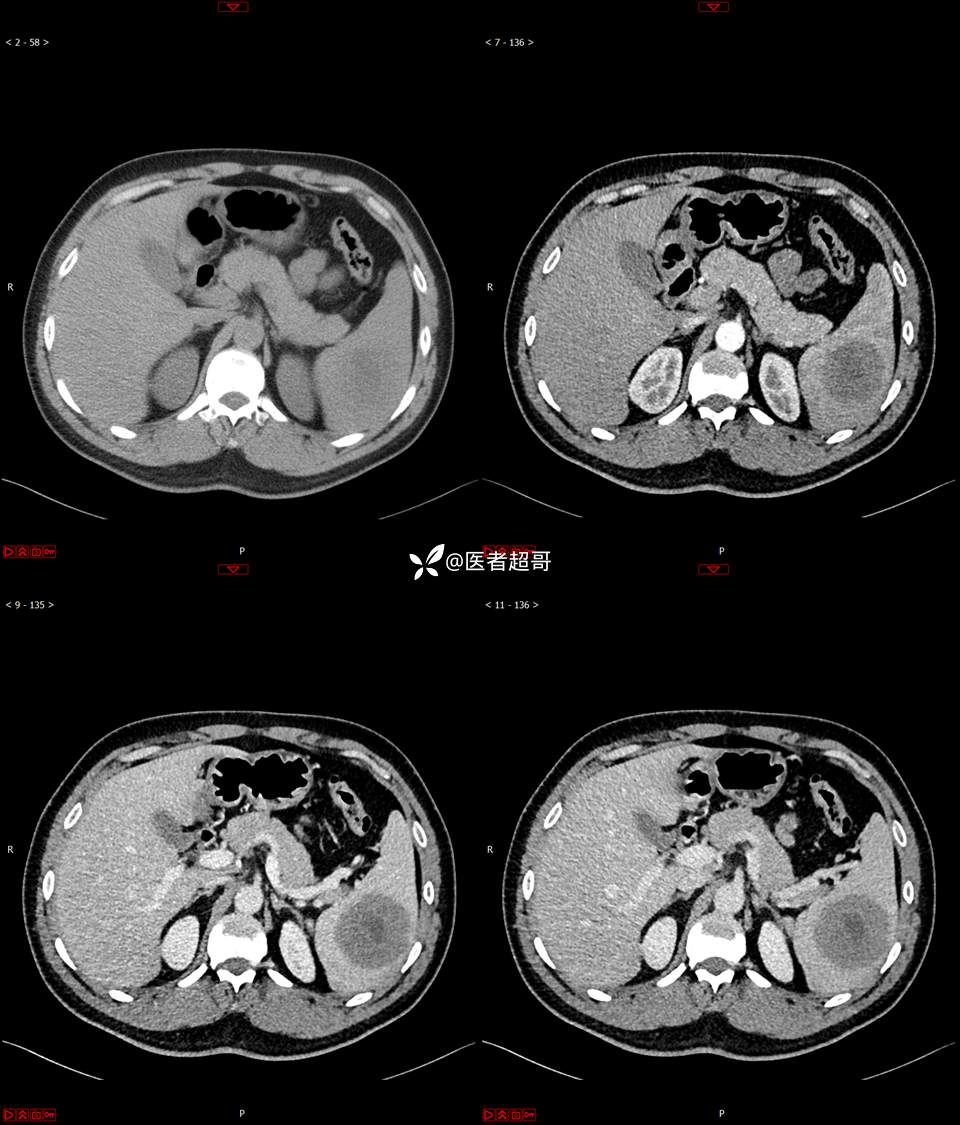

【影诊笔记738】脾脏低密度影,请诊断分析~~

男,33岁 0201215 01

主 诉:发现脾占位2月余。

现病史:患者2月余前体检行肝胆胰脾肾彩超提示脾占位性病变,未予特殊诊治,1天前于区人民医院行肝胆胰脾MR平扫提示脾脏占位性病变,左肾小囊肿,现患者无腹胀、腹泻,无恶心呕吐,无胸闷憋气等症状,今为求进一步治疗,患者来我院就诊,门诊以“脾占位性病变”收入院。患者自发病以来,一般情况可,神志清,精神可,饮食、二便正常,睡眠可,体重体力无明显改变。